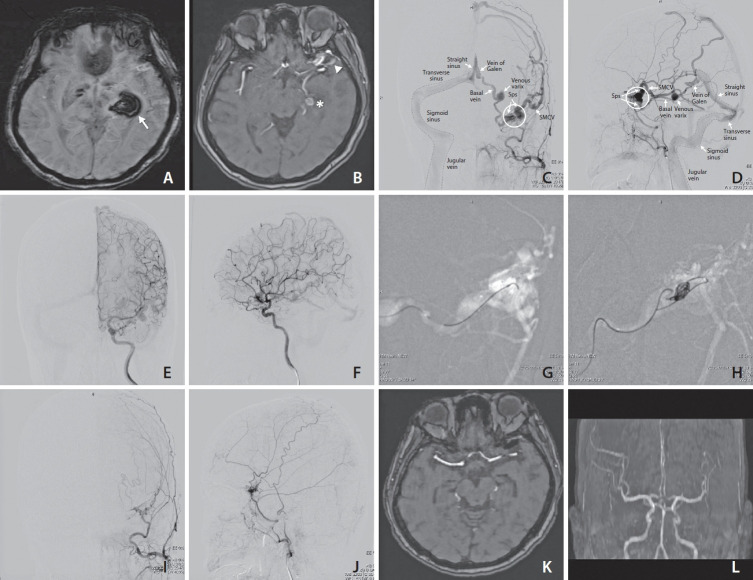

A patient in their early 60s presented with a headache and right-sided numbness. Imaging revealed a hemorrhagic lesion in the left thalamus and venous engorgement involving the left sphenoparietal sinus, with drainage through the basal vein of Rosenthal and the superficial middle cerebral vein. The trans-Galen approach was utilized for embolization, successfully obliterating the fistulas using coils without retrograde opacification. Post-procedure angiography demonstrated complete occlusion. This case underscores the trans-Galen approach as a safe and effective strategy for managing complex sphenoparietal sinus dural arteriovenous fistulas, providing direct access while minimizing complications and ensuring procedural success.